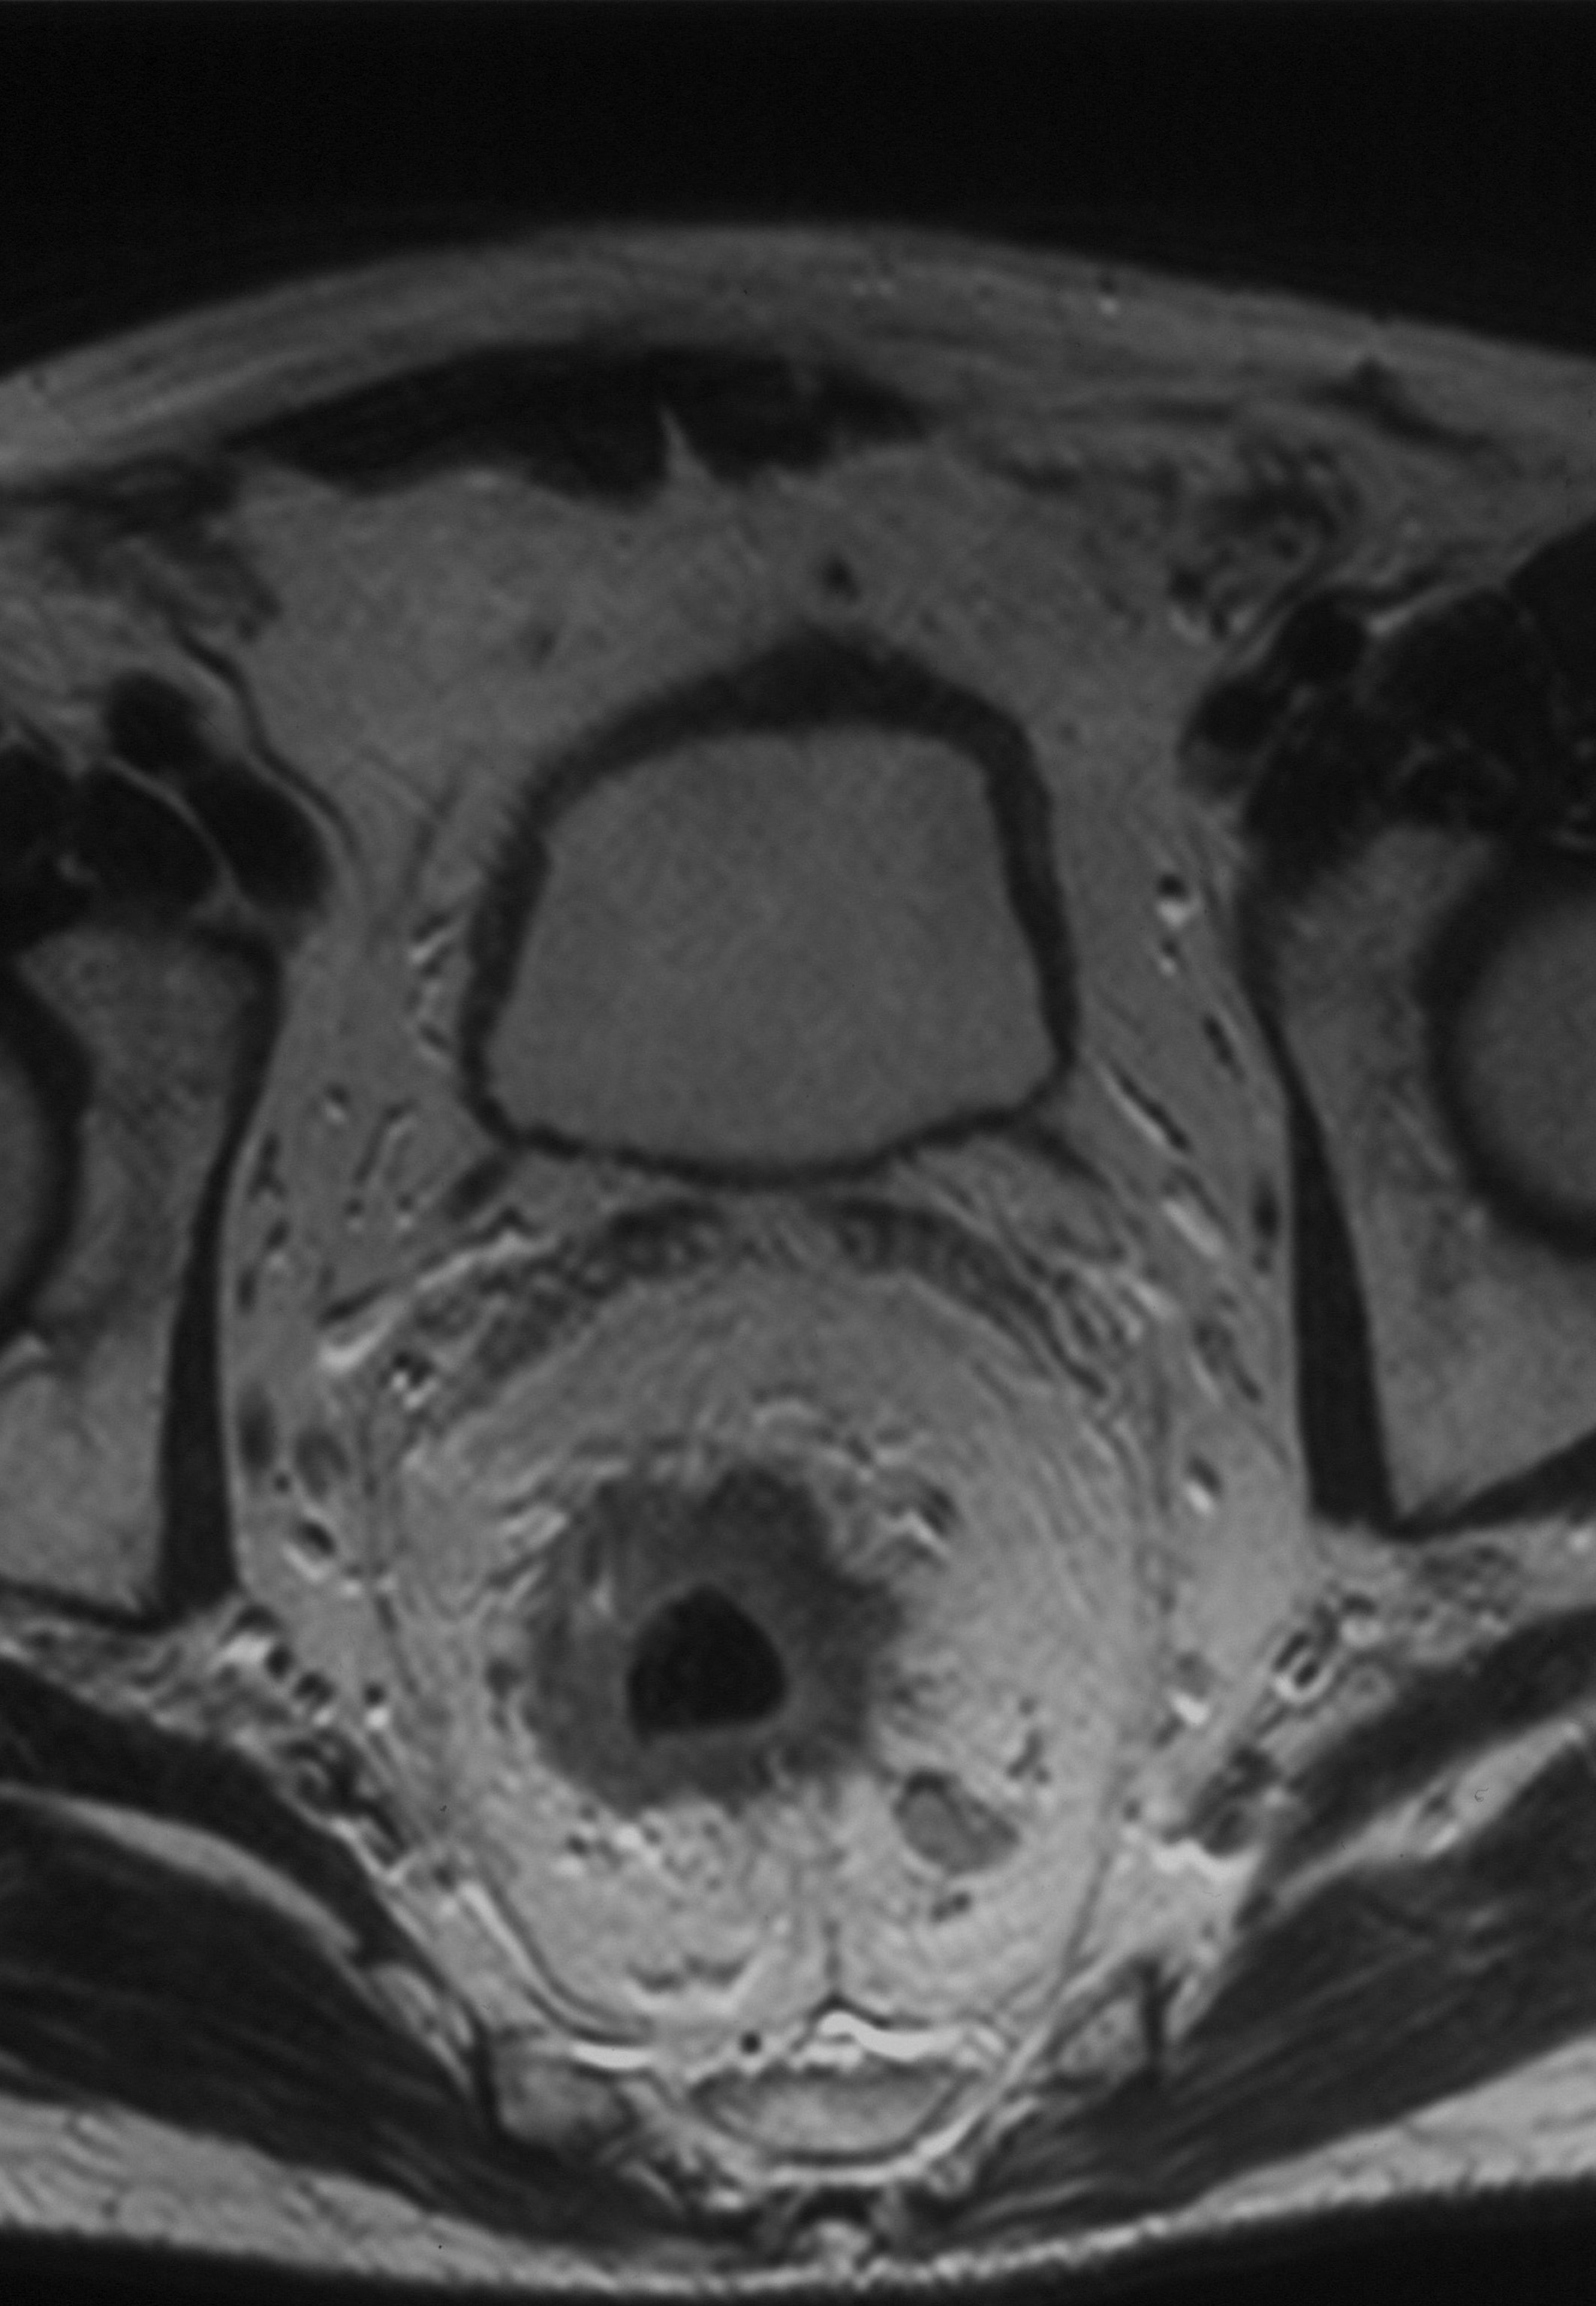

Fundamento. El objetivo de este trabajo es revisar la utilidad de la RM pélvica para la estadificación del cáncer de recto y establecer una correlación radiopatológica. Material y métodos. Se realizó un análisis retrospectivo de 120 pacientes con una edad comprendida entre 43 y 87 años a los que se realizó una RM pélvica para el estadiaje de cáncer rectal en nuestro hospital entre los años 2005 y 2010. Se catalogaron los pacientes de acuerdo a la clasificación TNM. Resultados. De los 120 pacientes, 80 fueron tratados con RT y/o QT neoadyuvante debido a que presentaban enfermedad localmente avanzada (T3-T4), afectación ganglionar (N1-N2) o metástasis resecables. Con los 40 pacientes que no fueron sometidos a tratamiento neoadyuvante se realizó una correlación entre los hallazgos de la RM y de la anatomía patológica con una precisión diagnóstica para predecir el estadio T del 72%, el estadio N del 60% y la distancia a la FMR del 87,5%. Conclusión. La RM pélvica es una técnica útil para la estadificación locorregional del cáncer de recto, obteniendo una buena correlación radiopatológica aunque la identificación de la afectación ganglionar es todavía un problema diagnóstico.Descargas